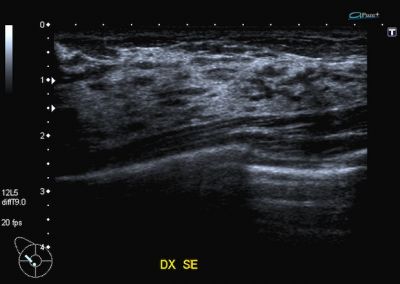

Resto in ascolto di un’altra me

che narra di vita e di speranza

un popolo di cellule che corre

spiato come sotto i riflettori.

Nessuno si domanda cosa penso

nel mio silenzio stesa sopra un fianco

il bianco dentro l’ombra d’una stanza

l’occhio che fissa un’immagine allo schermo

gli echi prodotti da un fascio d’ultrasuoni.

Io mi figuro un mare mosso nero

come la notte che s’agita tra i veli,

veloce come un gatto che svolta l’angolo.

E sogno un’oasi improvvisa nel deserto

una medaglia con due facce buone,

l’oblio da un lato, dall’altro la passione.

Dipenderà dal caso, dal mio ottimismo forse

o dal bacio tanto agognato d’una dea

che mai si degna di passarmi accanto...

Ma ora poco importa. Un mare mosso nero

e l’orizzonte dinanzi così chiaro!

Un fascio d’ultrasuoni mi sta dicendo

che va tutto bene. |